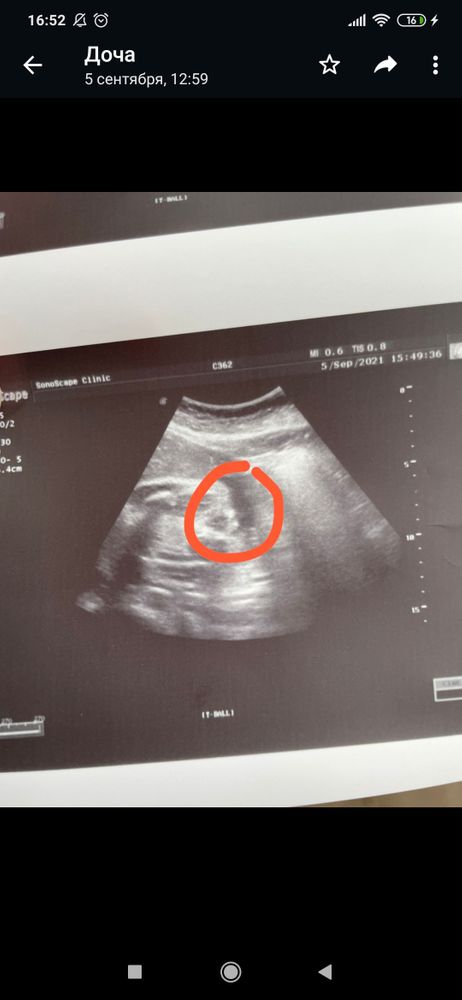

Xyliganka Tata

Алина , мне кажется точно мальчик)))

Вот такая девочка, а у вас богатырь))